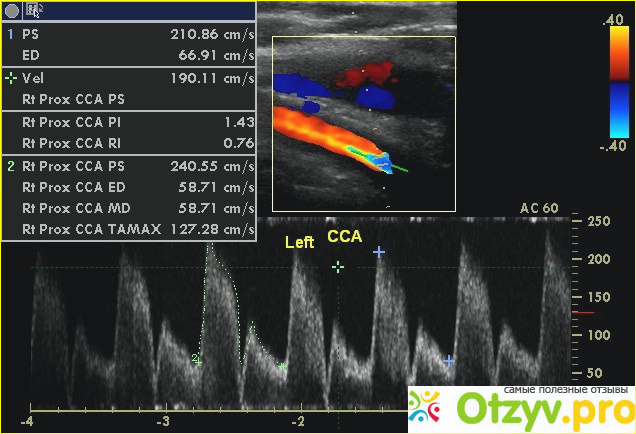

С помощью современных ультразвуковых методик успешно прогнозируются многие заболевания сосудов шейной области, по которым кровь поступает в мозг. Своевременно диагностируется появление холестериновых бляшек и показатели кровотока. Такое исследование сводит к минимуму риск повторного заболевания, способно предотвратить возникновения опасных состояний патогенной направленности.

Узи брахиоцефальных сосудов что это | Стенозирующий атеросклероз БЦС. |